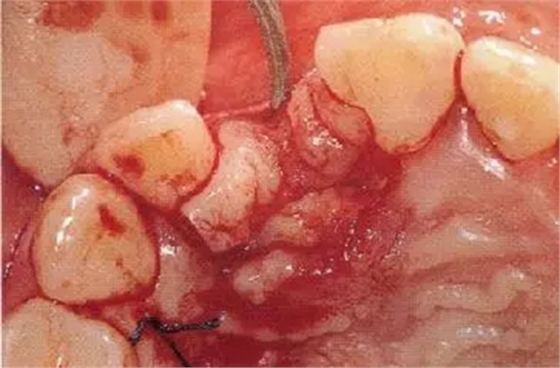

▲圖44-12,13

圖44-12 種植體植入4個月后。二次手術(shù)時同時進行結(jié)締組織移植(CTG),以增大牙齦。

圖44-13 二次手術(shù)后的狀態(tài)。

圖44-14

同時期的X光片。